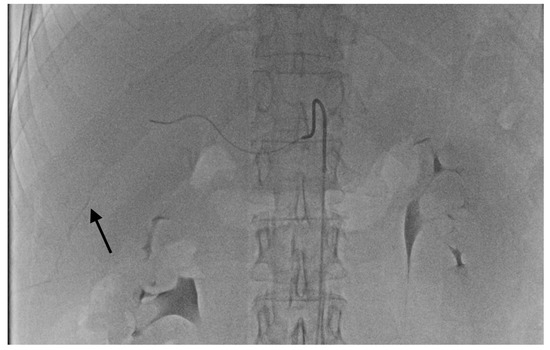

- Grade 2 stasis. Embolizate contrast at the level of tumor supply vessels (Figure 2).

- Grade 3 stasis. Embolizate contrast in subsegmental vessels (Figure 3).